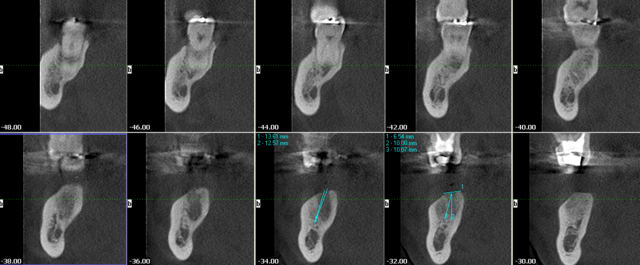

vite fait quelques copies d'écran de la Gendex CB 500 acquise il y a un an (avec le capteur de 1 ere génération)

Les modèles vendus actuellement ont un capteur optimisé pour les panos

pour les secteurs molaires